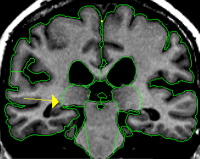

By drawing many sulci lines in the dorsal axial view, the mid axial view and the ventral axial view of the thalamus you can obtain a skeleton of the outline of the thalamus produced by "dots" marking the sagittally drawn sulci in the coronal view. This gives you a guide to find the best fit contour line.

The hypothalamic fissure serves as the inferior border of the thalamus and a dividing line between the thalamus and the ventral diencephalon (VDC). This border is marked by drawing sulci in the medial sagittal views of the thalamus and VDC. The hypothalamic fissure is seen most easily toward the midline in the sagittal view, therefore begin drawing the sulci lines on or close to the most medial sagittal slice. The fissure should be drawn as a line which cups the bottom of the thalamus beginning caudally and moving rostrally as far as possible. It is often advantageous to draw many sulci on consecutive sagittal slices, moving from medial to lateral, in order to see the full extent and curve of the fissure more accurately in the coronal view.

The inferior border of the thalamus can be drawn by connecting the "dots" that result from the sagittally drawn sulci lines in the coronal view.